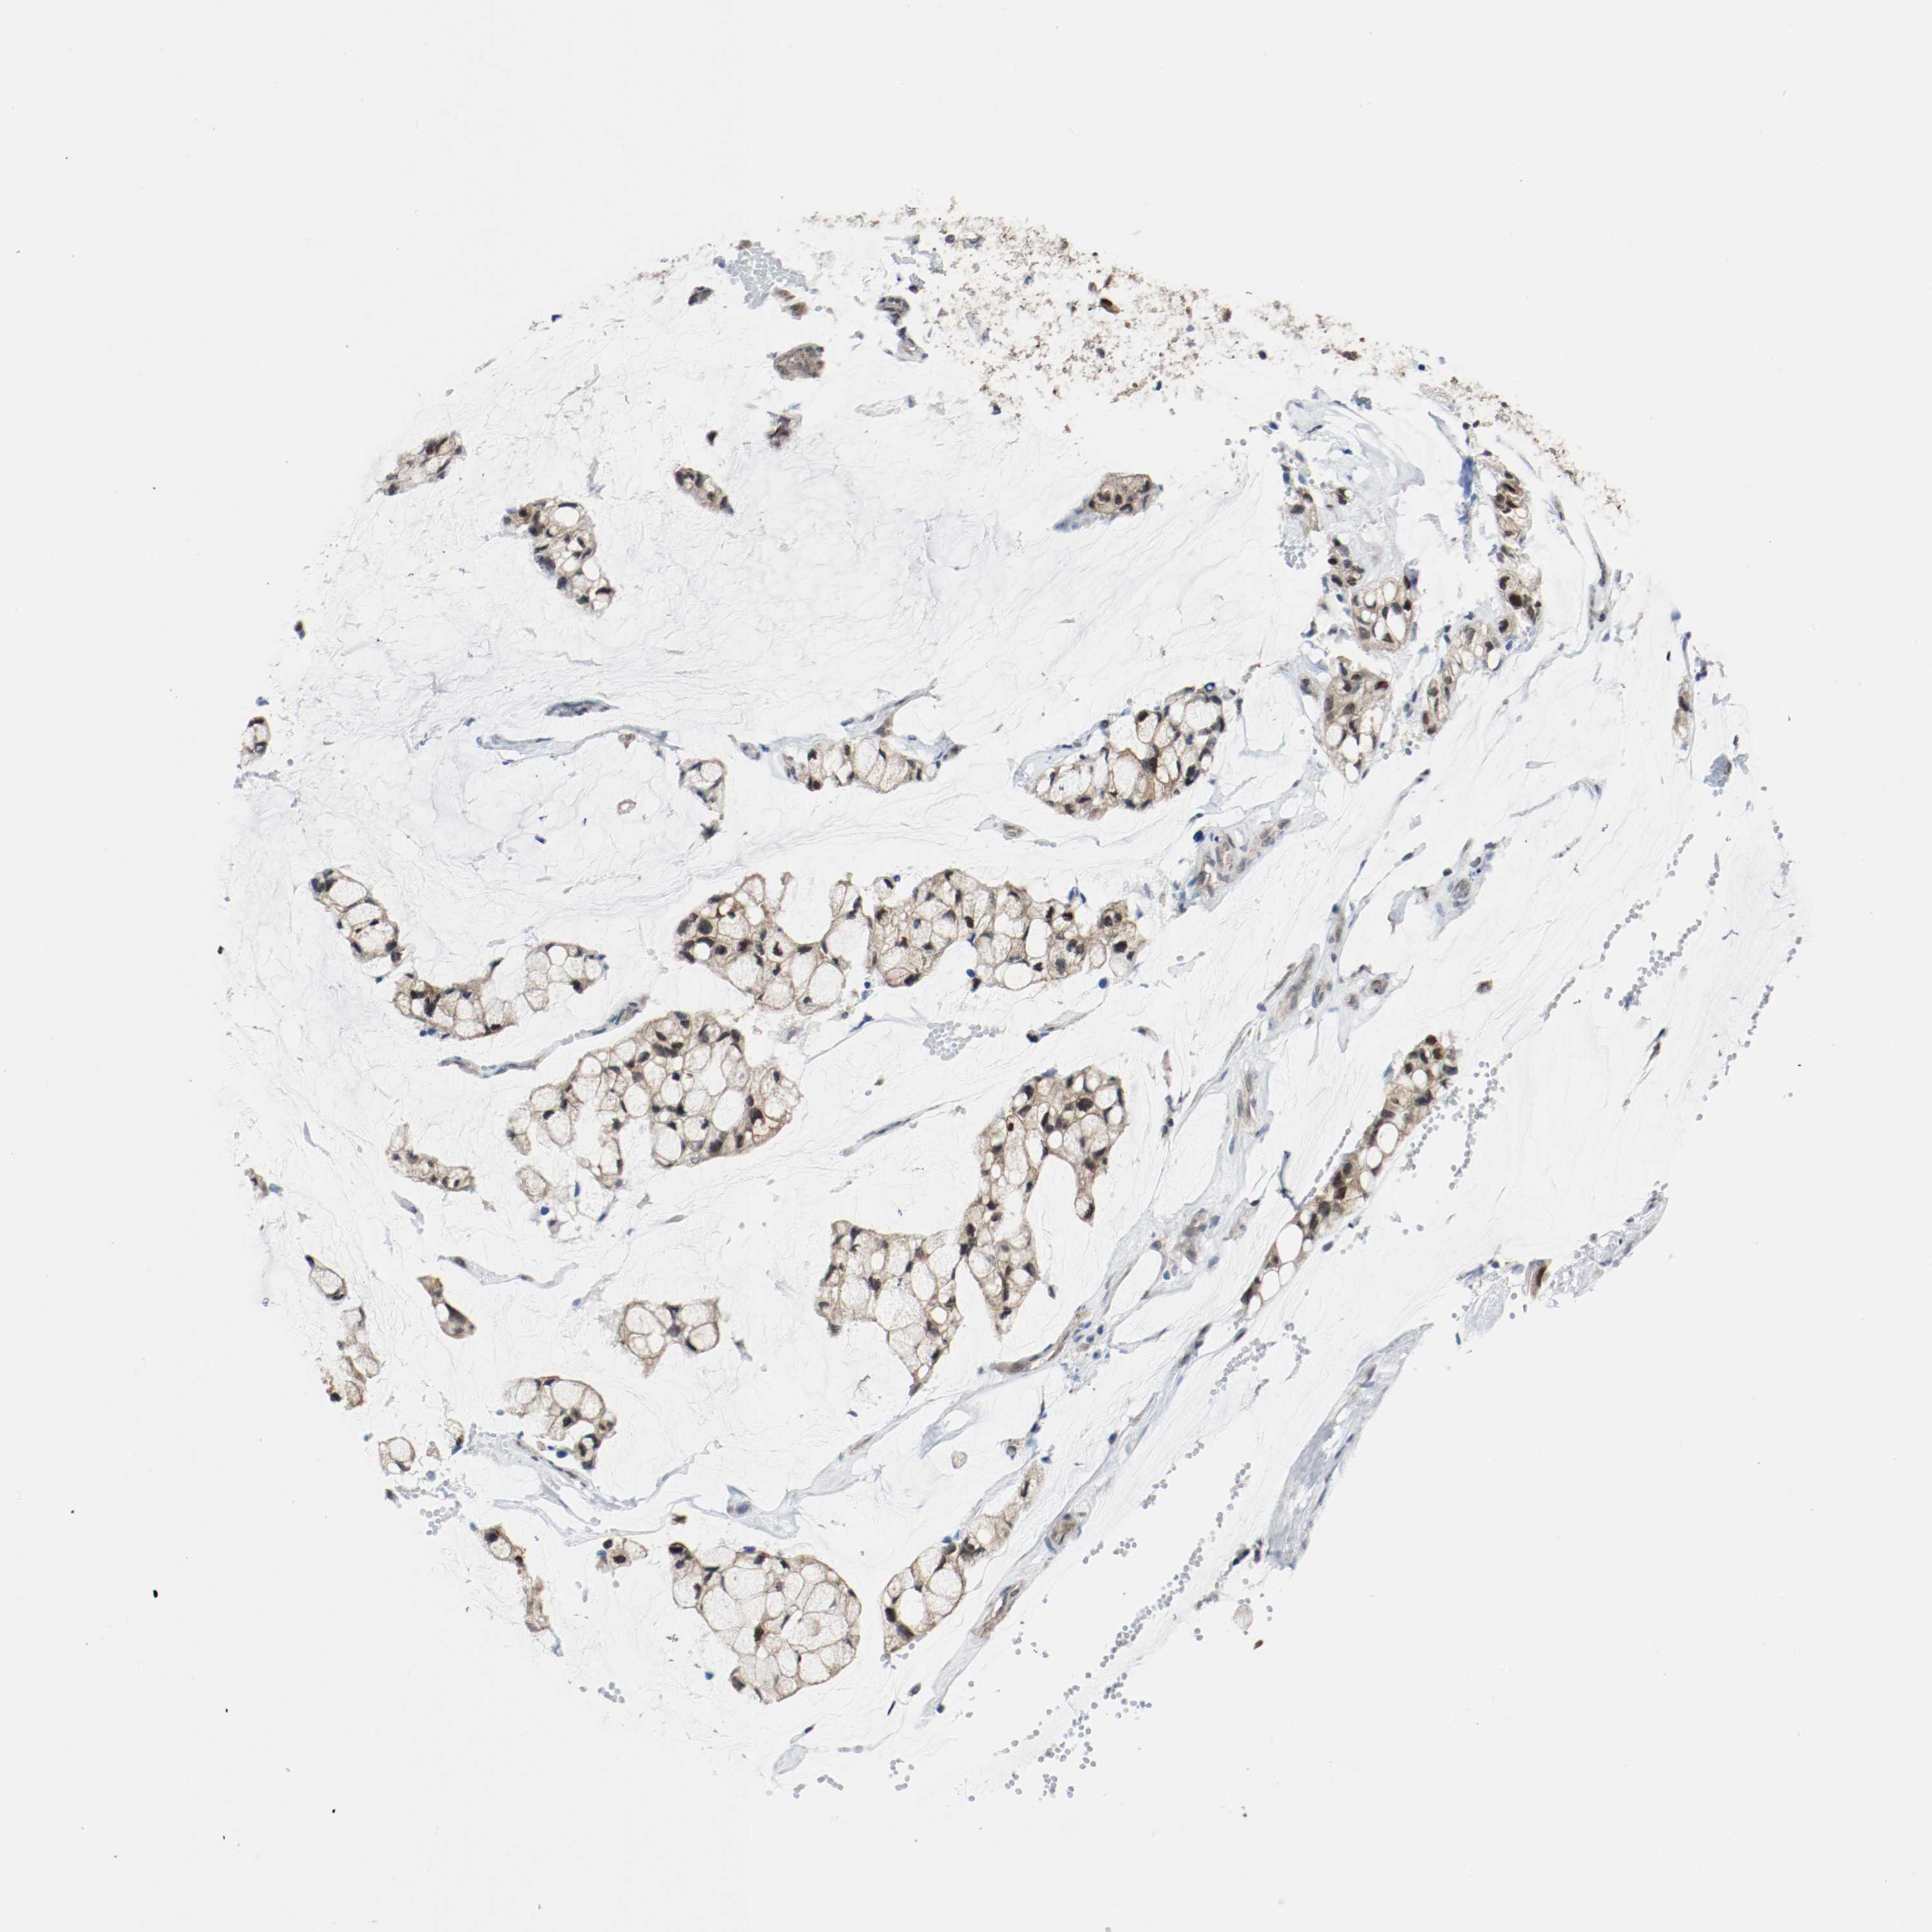

OVARIAN CANCER - Protein expressioni

A mouse-over function shows sample information and annotation data. Click on an image to view it in a full screen mode. Samples can be filtered based on level of antibody staining by selecting one or several of the following categories: high, medium, low and not detected. The assay and annotation is described here.

Note that samples used for immunohistochemistry by the Human Protein Atlas do not correspond to samples in the TCGA dataset.

Antibody stainingi

Antibody staining in the annotated cell types in the current human tissue is reported as not detected, low, medium, or high, based on conventional immunohistochemistry profiling in selected tissues. This score is based on the combination of the staining intensity and fraction of stained cells.

Each image is clickable and will lead to virtual microscopy that enables deeper exploration of all samples and also displays staining intensity scores, fraction scores and subcellular localization as well as patient and tissue information for each sample.

Carcinoma, NOS

Carcinoma, endometroid